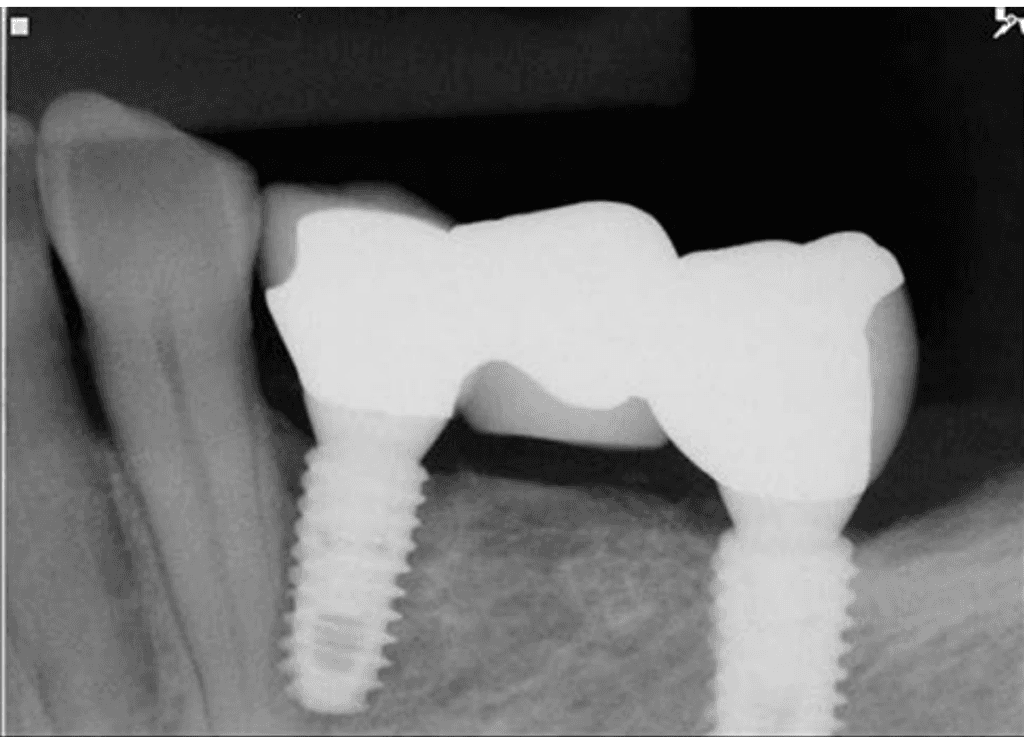

What to do if the implant is too close to the adjacent tooth?

Someone sent me this question not too long ago, with the accompanying photo and instantly I sympathized with the sender.

The implant was placed 0.8mm away from the adjacent tooth. Lots of questions you might have: